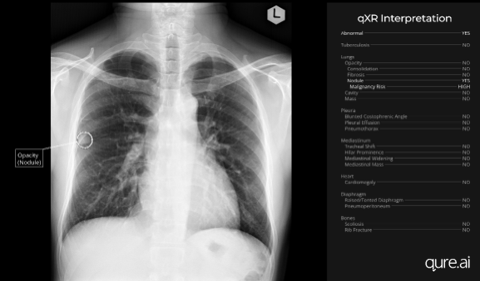

AI Can Detect Lung Nodules that Could Lead to Lung Cancer Nearly 3 Years Before Symptoms & Actual Diagnosis | Study finds https://t.co/uDxfdVZY5U via @Medical Device News Magazine